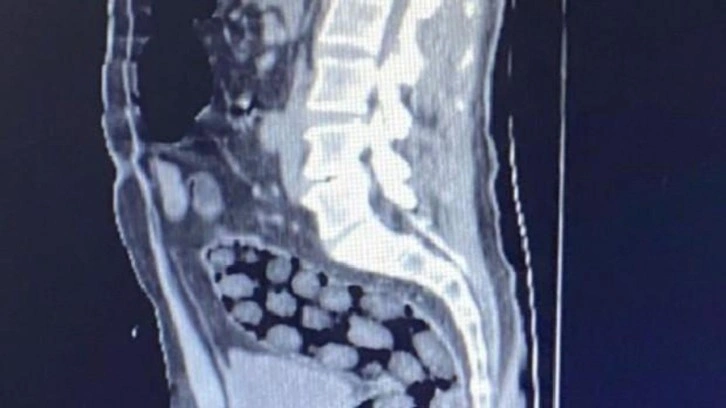

Bitlis Valiliğinden yapılan açıklamada, uyuşturucu ile mücadele kapsamında elde edilen istihbari bilgiler doğrultusunda Tatvan’da durdurulan bir otobüste yabancı uyruklu 3 yolcunun yakalandığı belirtildi. Açıklamada, “Bitlis Emniyet Müdürlüğü Narkotik Suçlarla Mücadele Şube Müdürlüğü ve İstihbarat Şube Müdürlüğü ekiplerince gözaltına alınan ve Tatvan Devlet Hastanesine sevk edilen şüphelilerin röntgen ve tomografi görüntülerinde mide ile bağırsaklarında çok sayıda yabancı cisim bulunduğu tespit edilmiş, yapılan tıbbi müdahale ile şüphelilerin paketleyerek yuttuğu toplam 91 adet daralı ağırlığı 1 kilo 126 gram metamfetamin maddesine el konulmuştur. Şüpheliler, çıkarıldığı adli mercilerce tutuklanarak cezaevine gönderilmiştir. Hemşehrilerimizin huzuru ve güvenliği için uyuşturucu madde imalatı, kaçakçılığı ve kullanımına karşı yürütülen kararlı mücadelemiz devam edecektir” denildi.